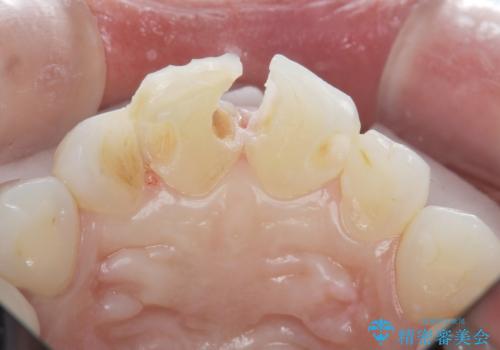

ラミネートベニヤの破折 ジルコニアクラウンによるやり替え

- 欠けてしまった前歯のラミネートベニヤと見た目の改善を求めて来院されました。

歯の大きさの不揃いと、虫歯の再発を認めたためラミネートのやりかえではなく一挙に問題の解決のできるジルコニアクラウンでの治療を計画します。